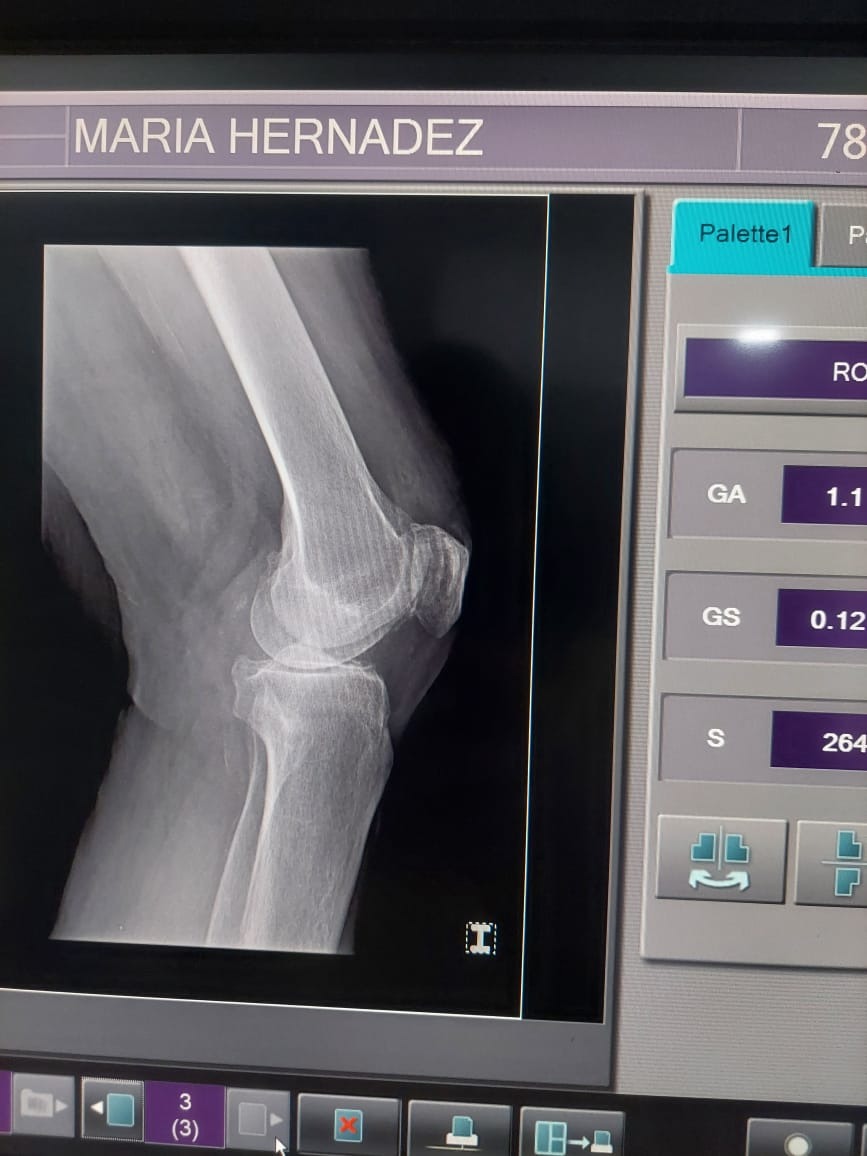

My mom has been diagnosed with severe osteoarthritis in her right knee, a condition that causes her constant and debilitating pain. After being evaluated by two medical specialists, both agreed that the only viable solution is a total knee replacement.

Mi mamá ha sido diagnosticada con artrosis severa en la rodilla derecha, una condición que le ha causado un dolor constante y limitante en su vida diaria. Después de ser evaluada por dos médicos especialistas, ambos coincidieron en que la única solución viable es una prótesis total de la rodilla derecha.